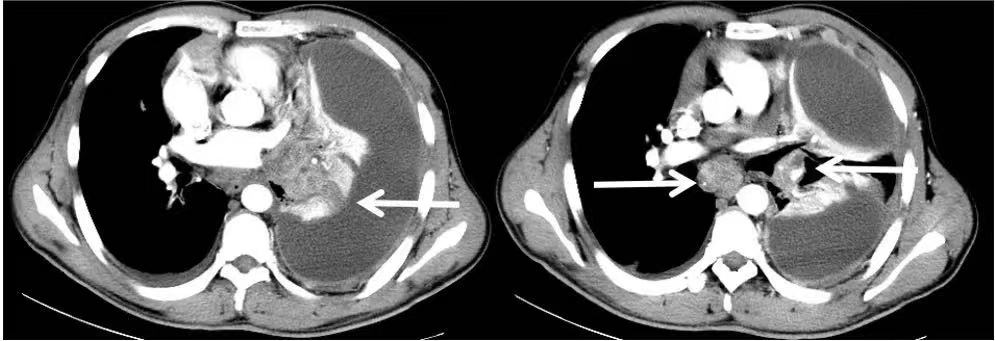

2015年5月,42岁的李先生出现了严重的咳嗽、胸闷、气短。在小诊所里输液抗炎了1个月,不见好转。他索性拍了个CT,报告上提示:左肺下叶占位,左肺不张,左侧大量胸腔积液。

2019年6月,李先生再次复查CT,肺部原发灶已经缩小到几乎看不见,胸腔积液也明显减少了。

可是好景不长,同年8月,李先生在干活的时候,突然出现头晕,而且逐渐加重,并出现双下肢乏力,腿脚不灵活等症状。紧急去医院复查,做了一个头颅MR,提示:颅内多发异常信号,转移瘤可能性大。